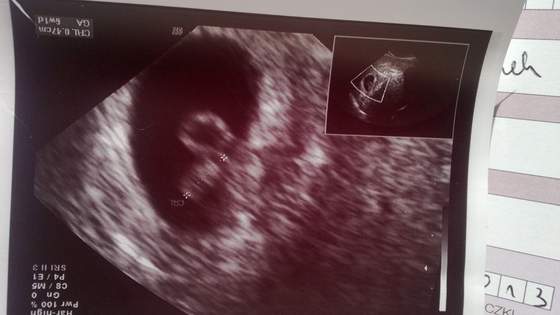

Byłam na pierwszej wizycie u gin w 5t2dc. Lekarz widział tylko pęcherzyk, a w środku nic. Powiedział, że jajo jest zagnieżdżone, ale jest za wcześnie, żeby określić, który to tydzień. Dostałam zdjęcie- pęcherzyk w środku czarny. Dodam, że z pierwszym dzieckiem była na wizycie w 5t3dc i już był pęcherzyk z widocznych środku "czymś" i lekarz od razu założył w tym dniu kartę ciąży. A teraz nie